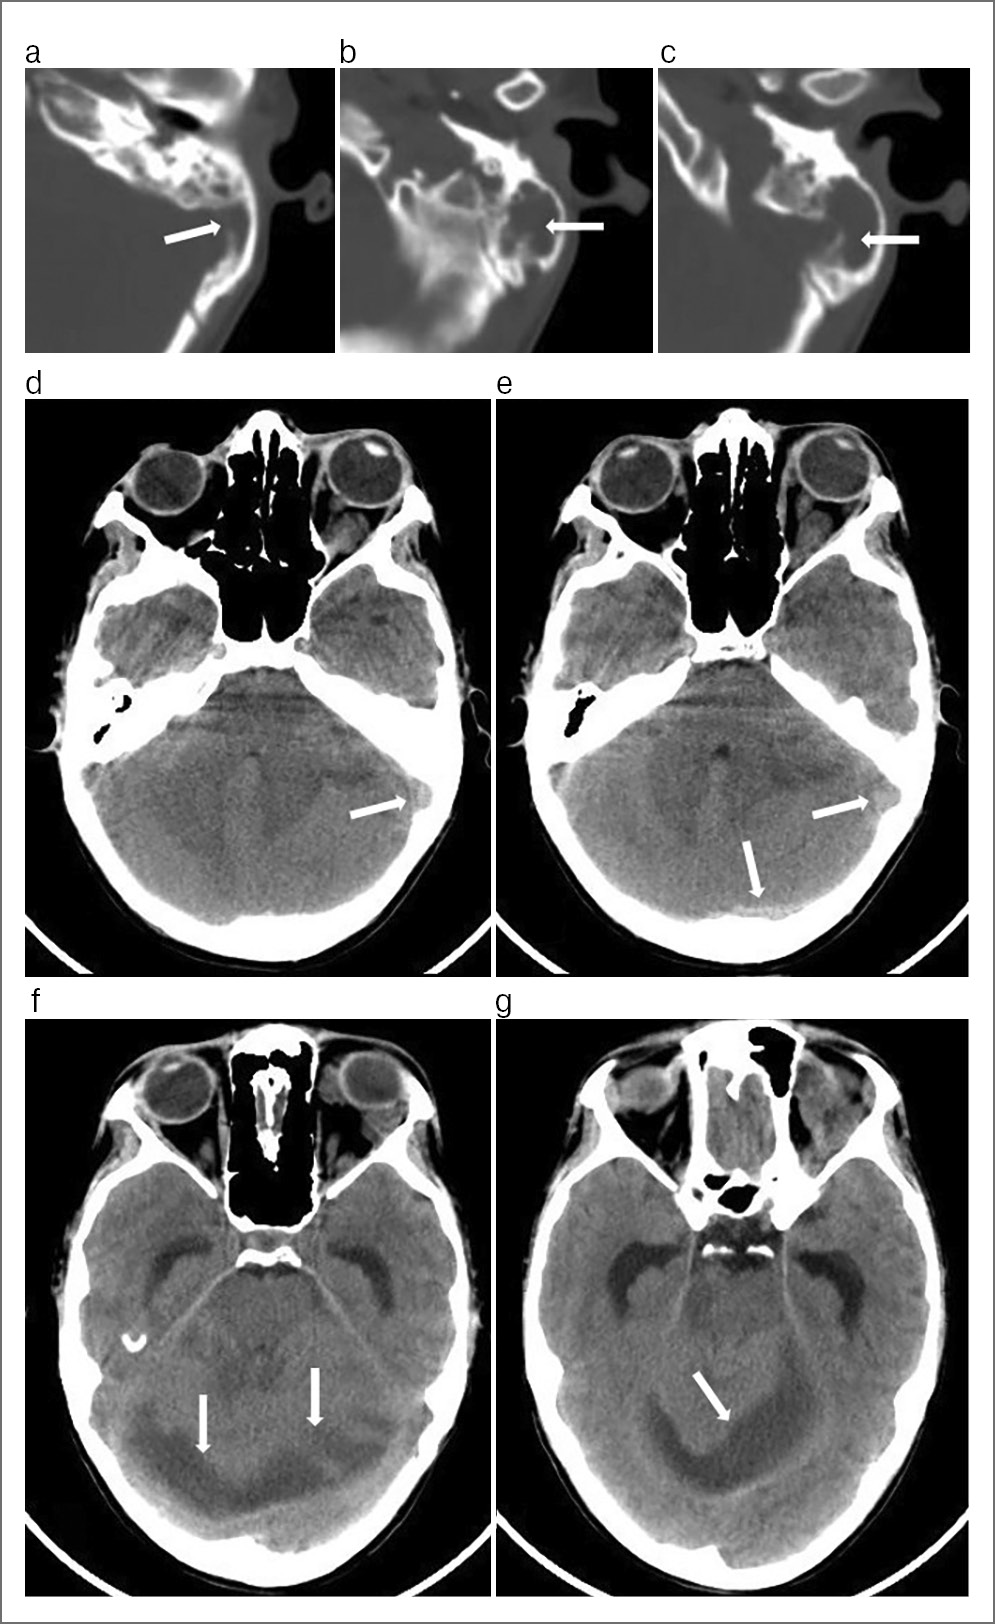

Консилиум (оториноларинголог, нейрохирург, невролог, реаниматолог, терапевт, клинический фармаколог, офтальмолог): комплексная оценка общего состояния больного: шкала Глазго – 15; SOFA – 1; APACHE II – 1; риск летального исхода по шкале APACHE II – 3,3. С учетом результатов КТ височных костей, ГМ (рис. 1) установлен диагноз: хронический эпитимпанит слева, холестеатома, мастоидит, отогенный менингоэнцефалит, тромбоз кавернозного, сигмовидного, поперечного синусов, субдуральный абсцесс задней черепной ямки, ССВР.

Рис. 1. КТ височных костей в аксиальной проекции (a–c) и ГМ без контрастирования в аксиальной проекции (d–g) пациента К., 16 лет. Диагноз: хронический эпитимпанит слева, холестеатома, мастоидит, отогенный менингоэнцефалит, тромбоз кавернозного, сигмовидного, поперечного синусов, субдуральный абсцесс задней черепной ямки, ССВР. Определяется инфекционная деструкция с истончением и аррозией задней грани пирамиды височной кости – стрелка (a), тотальное отсутствие воздушности ячеек левого сосцевидного отростка (b, c), обширная зона деструкции с образованием полости (стрелки), заполненной мягкотканным содержимым. На КТ ГМ определяются утолщение, извитость вен орбиты, левосторонний экзофтальм (d, e), повышение интенсивности сигнала в проекции левого сигмовидного и поперечного синусов (d, e – указательные стрелки), отек вещества ГМ, левой гемисферы мозжечка со смещением срединных структур ГМ. По ходу намета мозжечка определяется неправильной формы гипоинтенсивная зона (12–16 ед. Н), субдуральный абсцесс (f, g указательные стрелки); в левом полушарии мозжечка определяются гипоинтенсивные участки вещества ГМ (очаги энцефалита).